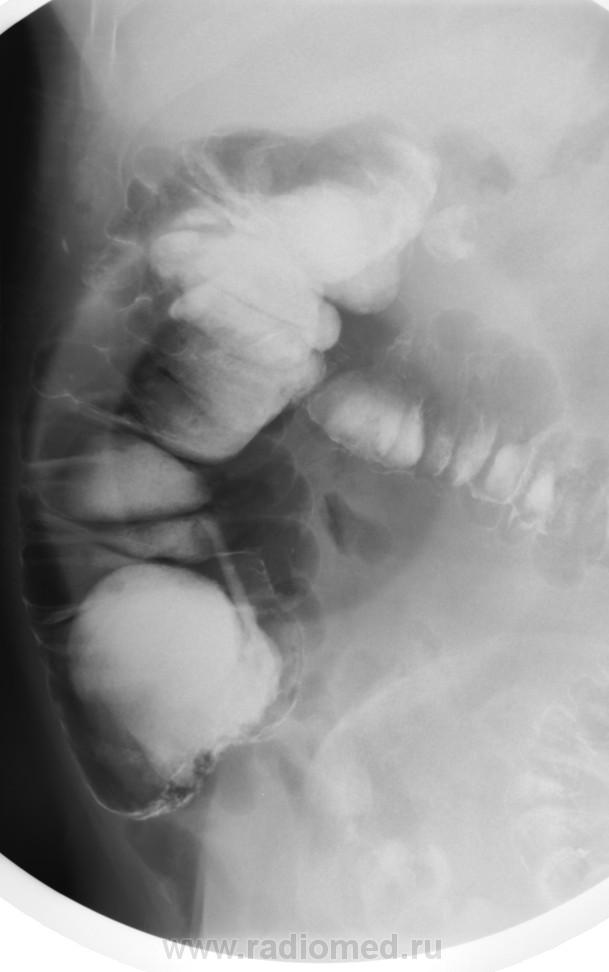

Такое ощущение, что слепая до конца не заполнилась. По-моему, я выставлял этот случай на сайте, но уж очень похоже. Никакими усилиями не возможно было заполнить слепую, хотя подозрения были. Только после т.н. опорожнения барий заполнил раковый канал.

Вполне может быть рак слепой кишки.

Согласен: купол слепой кишки выглядит ненормально, но возможно в результате операции. Вообще-то для большей ясности полагается контрастировать терминальный отд. подвздошной кишки. А колоноскопия здесь помогает не всегда.

ИМХО: слепая заполнена т.к. чётко видно обмазнный контрастом купол слепой кишки. Жаль, что не представлены R- граммы всех отделов толстой кишки.Показана фиброколоноскопия. При её безуспешности- РКТ брюшной полости, как компромиссный вариант УЗИ брюшной полости, для исключения синдрома поражения полого органа.